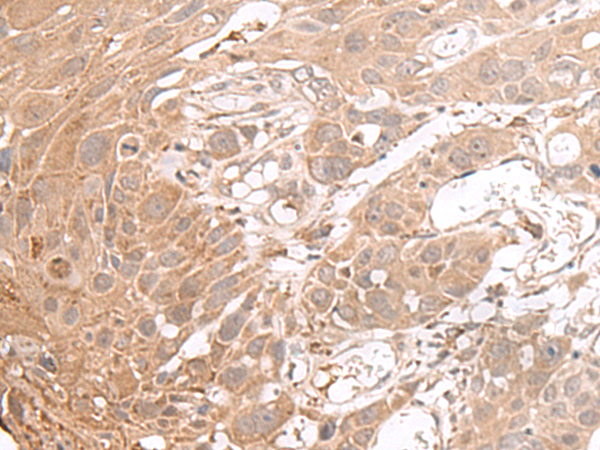

分类: 科研抗体货号: P06446别名: DVS27; IL1F11; NF-HEV; NFEHEV; C9orf26应用: IHC反应种属: Human